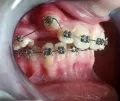

Ретенированный зуб можно вытянуть с помощью брекет-системы, а также не исключено, что он прорежется самостоятельно. И его останется установить на свое место.